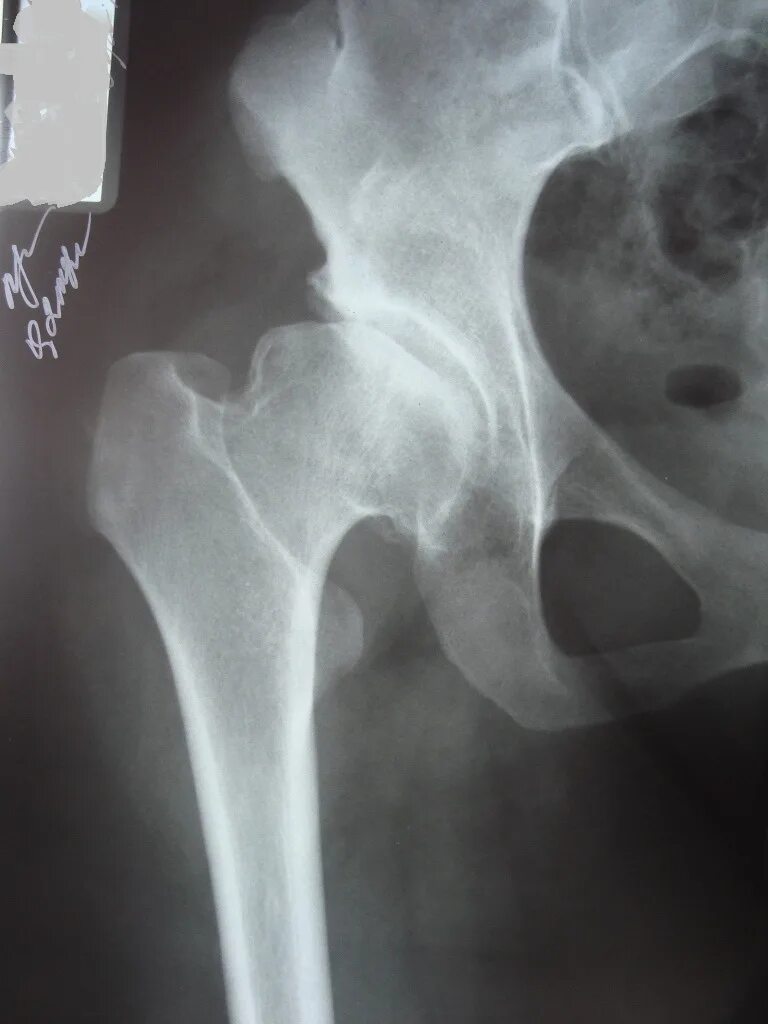

Коксартроз тазобедренного 1 степени симптомы